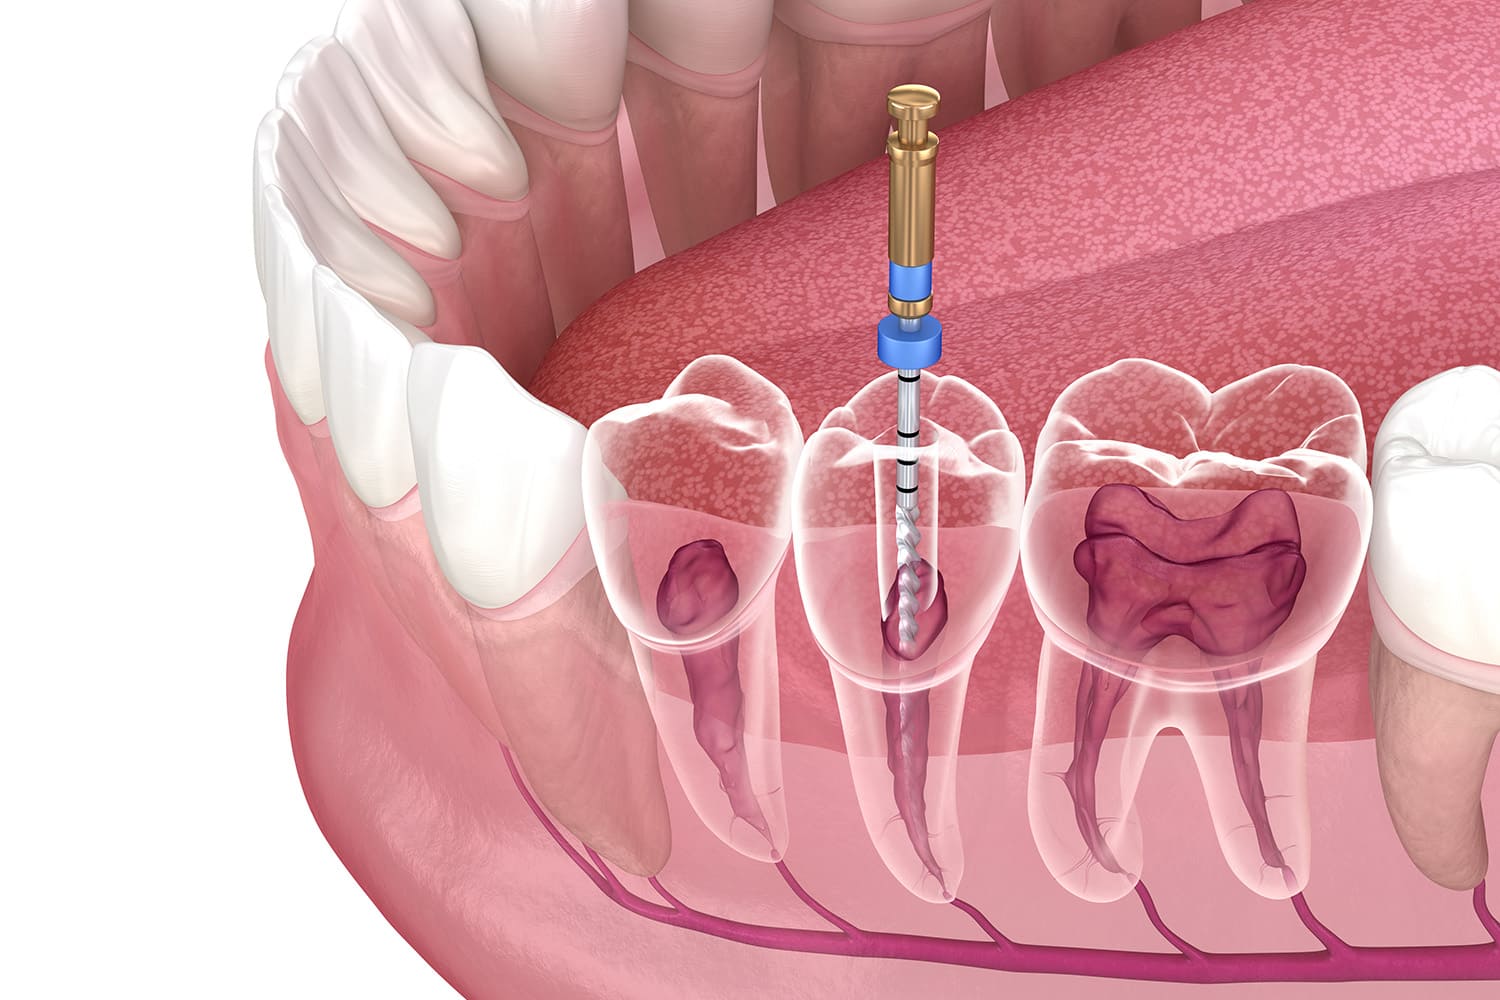

Caries

むし歯治療

むし歯治療は、介入のタイミングが重要です。患者さまの生活習慣やレントゲンの結果をふまえ、治療が必要かどうかを判断いたします。

痛みに配慮した治療を心がけ、お口の状態は写真を用いてご説明いたします。重度のむし歯でも、感染がなければ積極的に神経を残す治療を行い、歯の寿命を延ばすことに努めます。

詰め物の選択についても、長期的な安定と再発防止を見据えてご提案いたします。